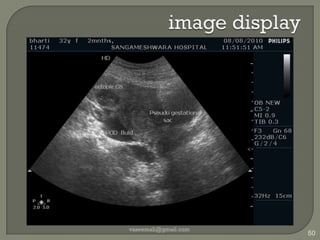

image displayvaseemali@gmail.com59depth